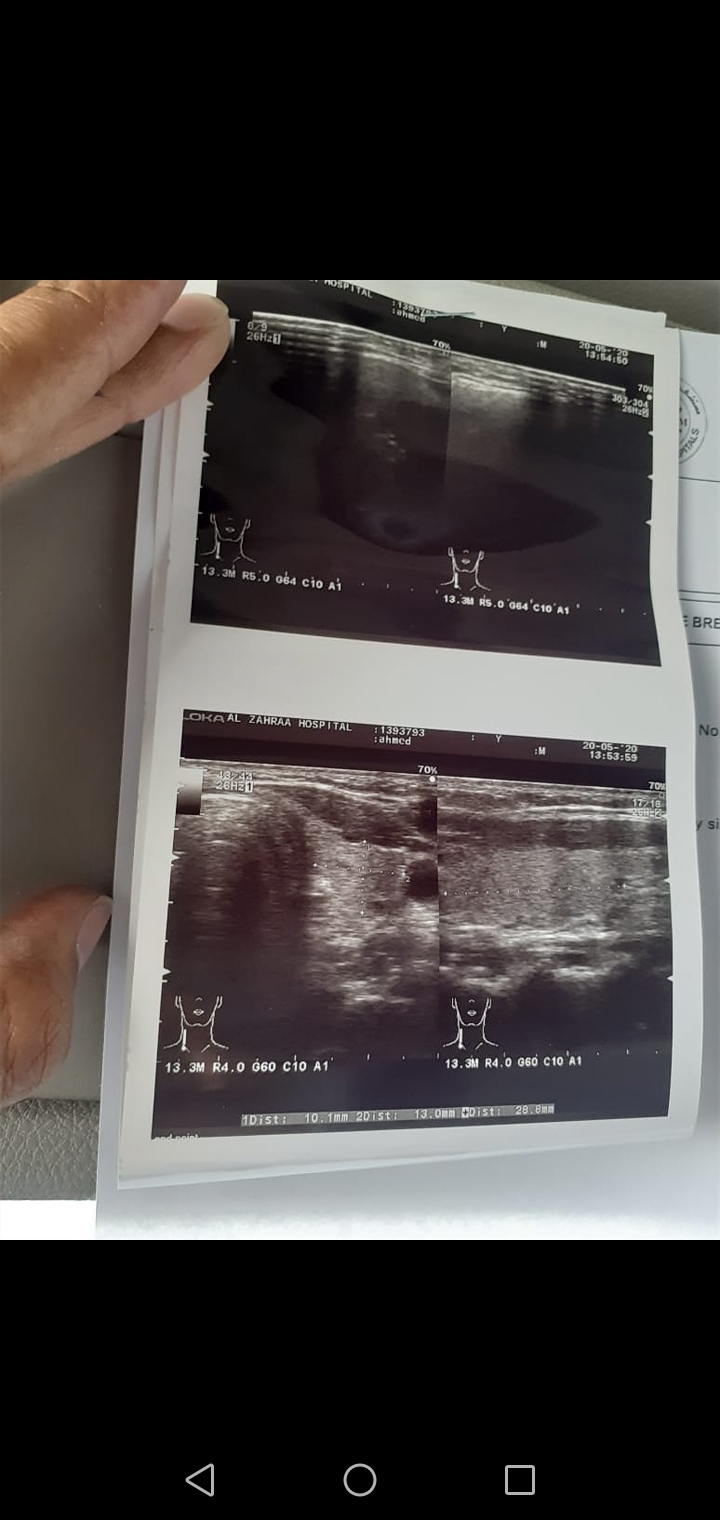

My husband is Haveing lymph node in neck, size is 18mm nd have cancer symptoms, he is taking madicine since 6 months but still in same condition, always feel burn nd pain in left side of neck, nd feel many other symptoms type of T.B, cancer, Please please reply what to do.

Dear please get a fine needle aspiration cytology and a biopsy of the lymph node

to have a clear picture regarding the cause of enlarged lymph node